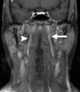

Enlarged lateral retropharyngeal lymph node